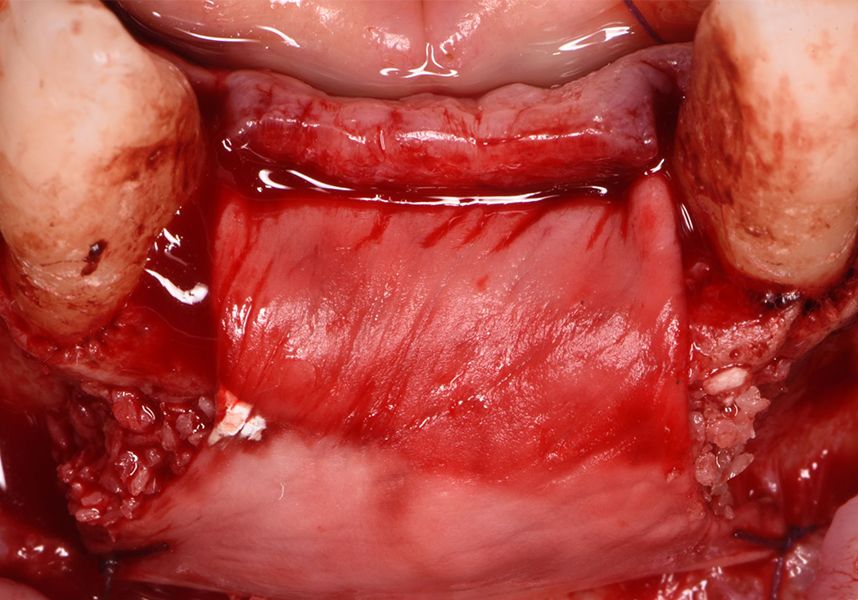

To treat the defect, bone regeneration was carried out simultaneous to the surgical process, with an autologous bone graft from the patient. In the internal part of the graft we used autologous cortical bone obtained by scraping (Safescraper) and from the biological drilling, at low revolutions and without irrigation, from the other implant beds. In the external layer of the regeneration we used a xenograft (Genoss, Osteogenos) and this was covered with a reabsorbable collagen barrier membrane (Evolution STD, Osteogenos).

The membrane was sutured with PGA reabsorbable suture to the periosteum to secure it, thus avoiding subsequent reentry to remove fixings such as tacks.